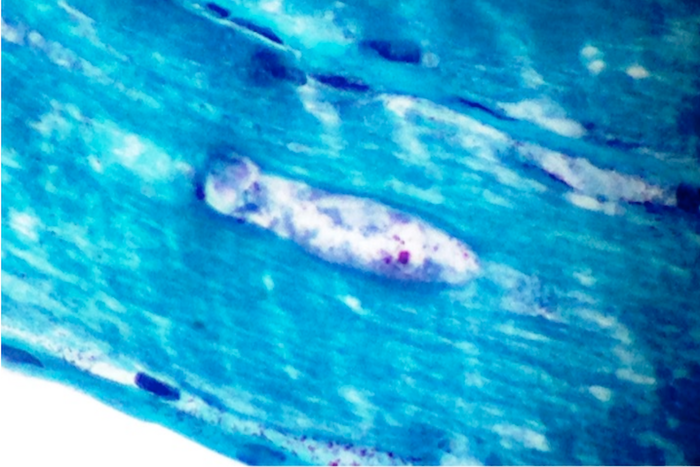

- The Gomori Trichrome stain shows "rimmed vacuoles", although the extent of myofibers having classic rimmed vacuoles varies (Dubowitz: Muscle Biopsy: A Practical Approach, 2013, 4th Edition)

- The vacuoles disrupt the myofiber architecture and can lack NADH-TR staining (Dubowitz: Muscle Biopsy: A Practical Approach, 2013, 4th Edition)

- Gomori trichrome shows rimmed vacuoles and can show ragged red fibers in areas

- 15-21 nm tubulofilaments in sarcoplasm